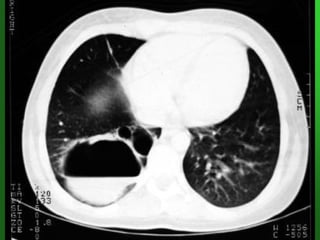

Clinical manifestations of

respiratory syncytial virus

(RSV). Chest

radiography performed in a

child with RSV bronchiolitis

revealed

bilateral hyperinflation from

air trapping, patchy

atelectasis from airway

plugging, and peribronchial

thickening from

lymphomonocytic

infiltration. Patients with

severe disease may also

have features more

consistent with pneumonia,

with areas of interstitial

parenchymal

infiltration.

•• Los hallazgos más frecuentes son:Los hallazgos más frecuentes son:

•• HiperinsuflaciónHiperinsuflación pulmonar bilateral ypulmonar bilateral y

engrosamientosengrosamientos peribronquialesperibronquiales (patrón(patrón

obstructivo,obstructivo, propio de niños mayores de 3propio de niños mayores de 3--66

meses).meses).

•• Atelectasias, infiltrados (neumonía viral)Atelectasias, infiltrados (neumonía viral)

(patrón restrictivo más frecuente en menores(patrón restrictivo más frecuente en menores

de 3 meses).de 3 meses).